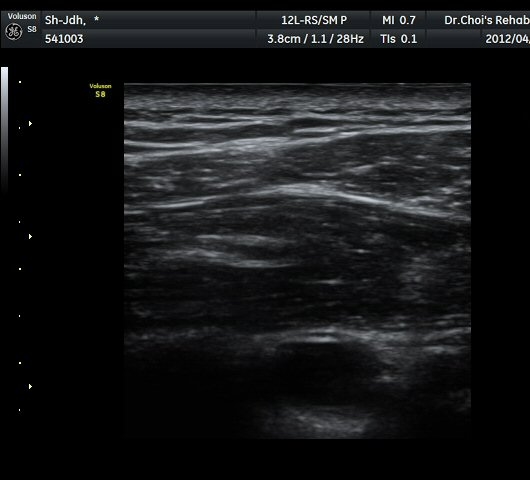

À̵ιڱ٠Ⱦ´Ü¸é°Ë»ç¿¡¼­ À̵ιڱٰÇÀÇ ºñÈĸ¦ º¸ÀÓ(»çÁø 1, 2).

À̵ιڱٰú ÀÌ¿ôÇÑ °ß°©ÇÏ±Ù°Ç »óºÎ¿¡¼­ ±¹¼ÒÀûÀÎ ¿¬°á¼º ¼Ò½ÇÀÌ °üÂûµÊ(»çÁø 3).

¾î±ú µÚ °üÀý¼ø °Ë»ç¿¡¼­ °üÀý¼ø Ç¥Ãþ¿¡ Àú¿¡ÄÚ ¼ö¾×Àú·ù°¡ °üÂûµÊ(»çÁø 4).

ŽÃËÀÚ¸¦ Á» ´õ µÚ·Î À̵¿ÇÏÀÚ °üÀý¼ø ³»Ãø °¡½Ã°üÀý¿À¸ñÆÐÀÓ(spinoglenoid notch)¿¡

¿øÇü¸ð¾çÀÇ Àú¿¡ÄÚ ³¶Á¾ÀÌ °üÂûµÊ(»çÁø 5, 6).